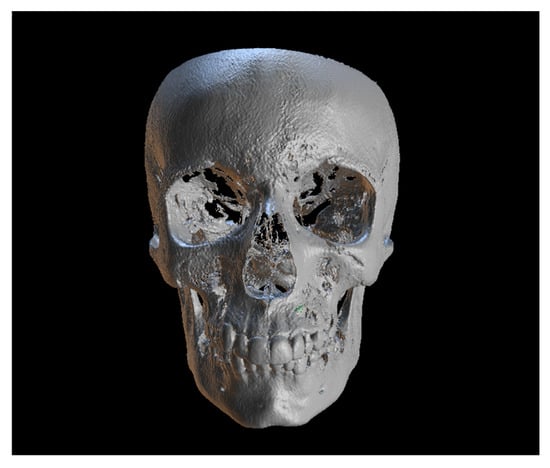

First step: Segmentation of Teeth and Skull Bones from Initial CBCT.

Each CBCT scan was opened in the Blue Sky Plan 4® software. The CBCT was automatically segmented to isolate the skull bones from the upper teeth, creating a skull model. The maxillary bone was used as a reference structure. To generate a precise model of the IC, including the cusp tip and apex, automatic tooth segmentation was performed. The axial view was used to verify whether the cusp tip and apex were accurately included in the model. In some cases, manual segmentation was necessary to ensure their integration. The final model combined both the skull and the IC. This process was carried out only when both (initial and after canine crown eruption) CBCT scans of a patient were available.

Second step: Overlay the Two CBCTs.

The two models were superimposed and aligned using at least ten points located on the skull and then saved as an STL file.

First step: Tooth Segmentation from Initial CBCT Scan.

Since the IC is not visible in the initial STL, it was necessary to know its three-dimensional location. As performed in the other method, the initial CBCT scan (Figure 2) was opened in the program, and all teeth were segmented. Although Figure 2 shows the skull model, only the teeth segmentation is necessary for this method. A small cut was made to allow visualization of the IC (Figure 3).